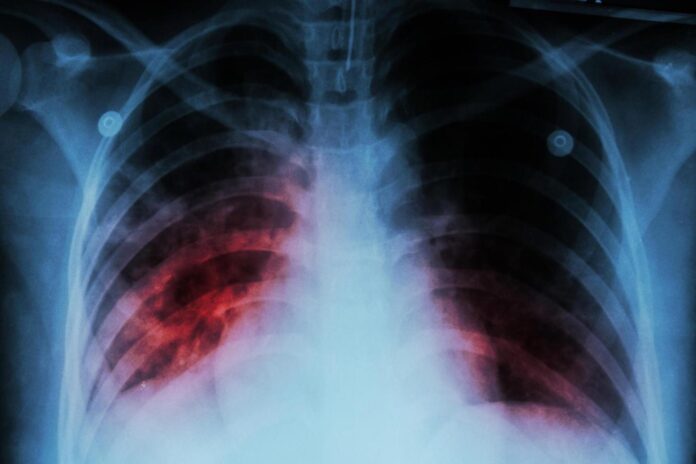

Tuberculosis is a respiratory disease caused by bacteria, according to the U.S. Centers for Disease Control and Prevention.

TB primarily affects the lungs and can spread to other parts of the body, such as the brain, spine, lymph nodes and kidneys.